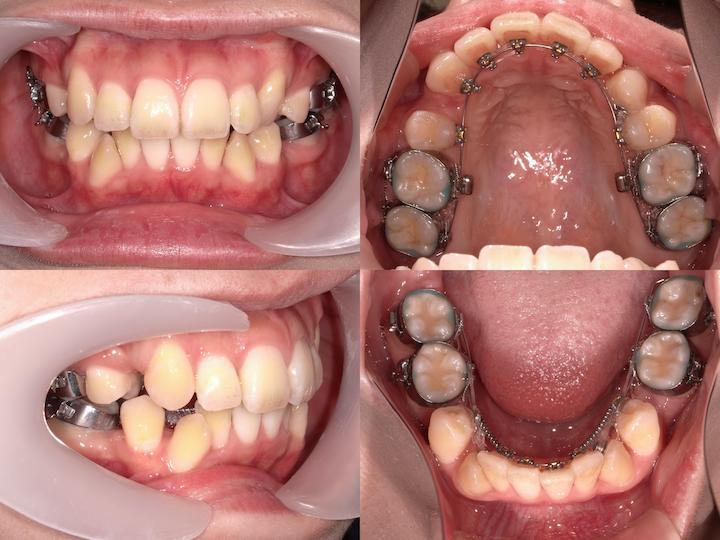

上下顎ともに舌側矯正装置(リンガルブラケット)を使用し、審美性に配慮した治療を実施いたしました。アンカレッジコントロール

上顎においては、犬歯の後方牽引時における大臼歯の不要な近心移動を防止するため、正中口蓋縫合部にPLAS(パラタルレバーアームシステム)を植立し、マキシマムアンカレッジ(最大固定)を確立しました。これにより、上顎大臼歯を確実に固定し、治療後の口元の形態を維持することができました。

一方、下顎においては、AngleⅡ級臼歯関係の改善を図るため、大臼歯の近心移動を許容する治療メカニクスを採用いたしました。